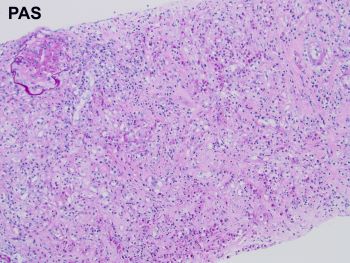

Case History:

A 64 year-old man with history of clear cell renal cell carcinoma s/p nephrectomy (2021) presents with scrotal pain and firmness. Ultrasound reveals a 2 cm solid lesion. Serum tumor markers (hCG and AFP) were normal. The tumor was negative for SALL4, OCT3/4, AFP, and showed focal patchy positivity for pancytokeratin (focal). PAX8 was weakly positive. Additional stains are displayed in the pictures.